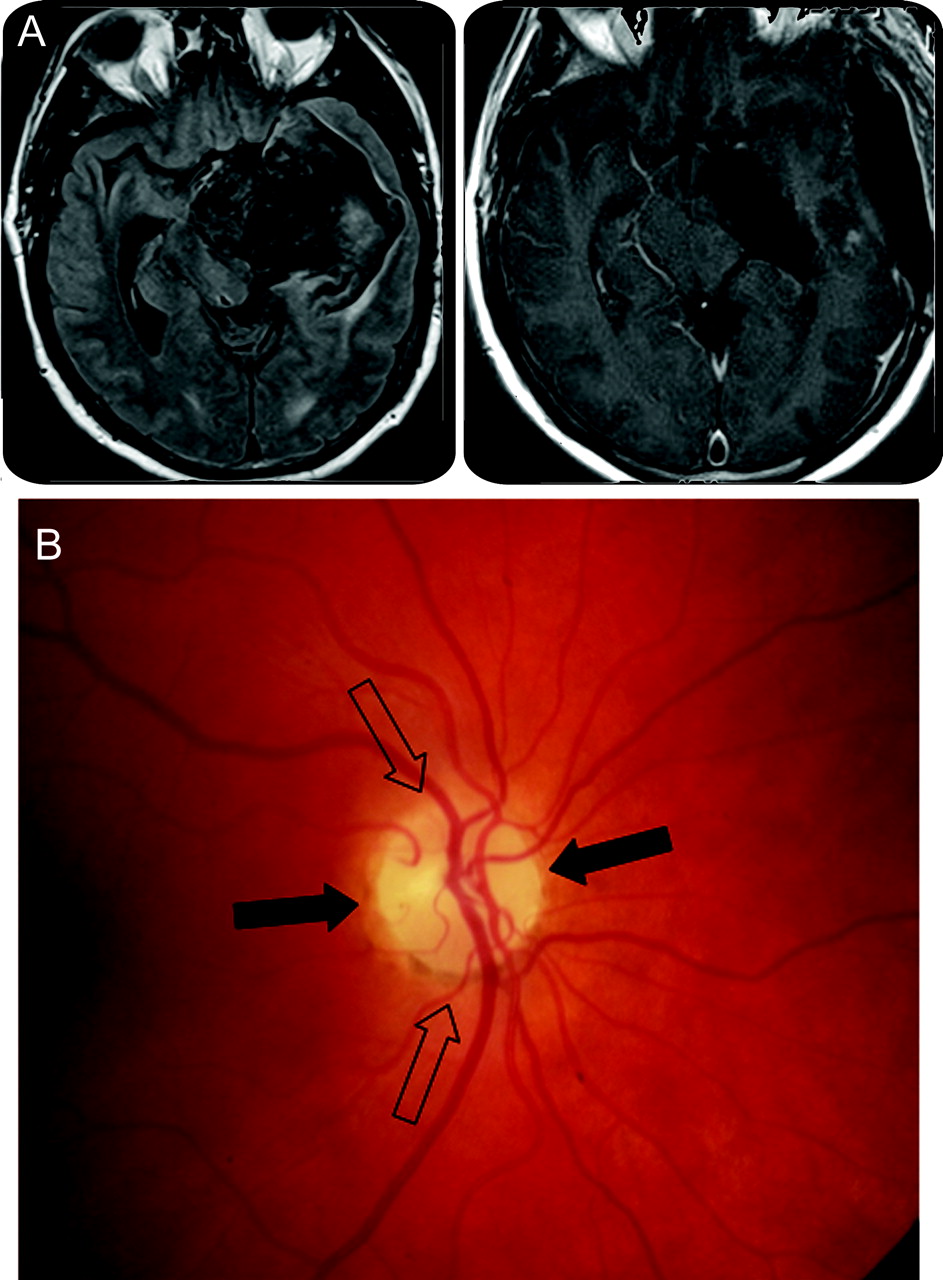

(一)术前和术后MRI。(B)领结萎缩。从视网膜鼻纤维视神经盘和纤维鼻窝但时间盘项目中央部分的视神经(黑色箭头)。纤维的视网膜颞形成两极视神经盘(空心箭头)。

手术后,他指的眼科评估一个完整的左第三个神经麻痹术中损伤的结果。他的术后视力20/25双眼与正常色觉。有一个正确的RAPD。眼底镜检查显示视神经萎缩的领结模式对视神经盘(图左盘显示,B),而温和,分散苍白。Goldmann视野检查发现一个几乎完整的正确的同向偏盲。一年之后第二个操作,左边第三个神经麻痹了,他只有一个小仰角赤字在左眼但没有复视主注视或阅读位置。

轴突从视网膜鼻相对应的视神经盘和鼻一半的黄斑(位于阀瓣颞)主要分布在圆盘的横向部分。这些轴突侧眼睛和促进整个时间字段注定要交叉的交叉。两极的视神经盘是由纤维形成的视网膜颞(图B)。由于这种特殊的组织,交叉的纤维损伤导致萎缩在中央部分的圆盘极点(领结萎缩),和损害颞纤维主要影响两极保护盘的中心部分。2重要的是要记住,领结萎缩可以单方面(侧眼视神经束损伤)或双边(交叉的病变)。